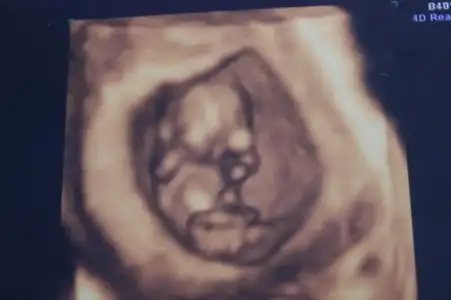

Eki Görüntüle 473828 gordugunuz gibi ust taraftaki simgedende anlasildigi gibi eger cikinti paralel ise kiz

yok 30°lik bir aciyla yukari dogru bakiyorsa %99 oglunuz olacak demektir simdi bi kac ornek resimler daha koyacagim kiziminkide dahil

Eki Görüntüle 473829 bu bir erkek bebek genital nub cikintisi gayet yukarda

Eki Görüntüle 473831 simdi burada cikintilara bakin eger bel popo cizgisine paralel ise kiz

yok 30 derecelik bir aciyla yukari bakiyorsa erkek